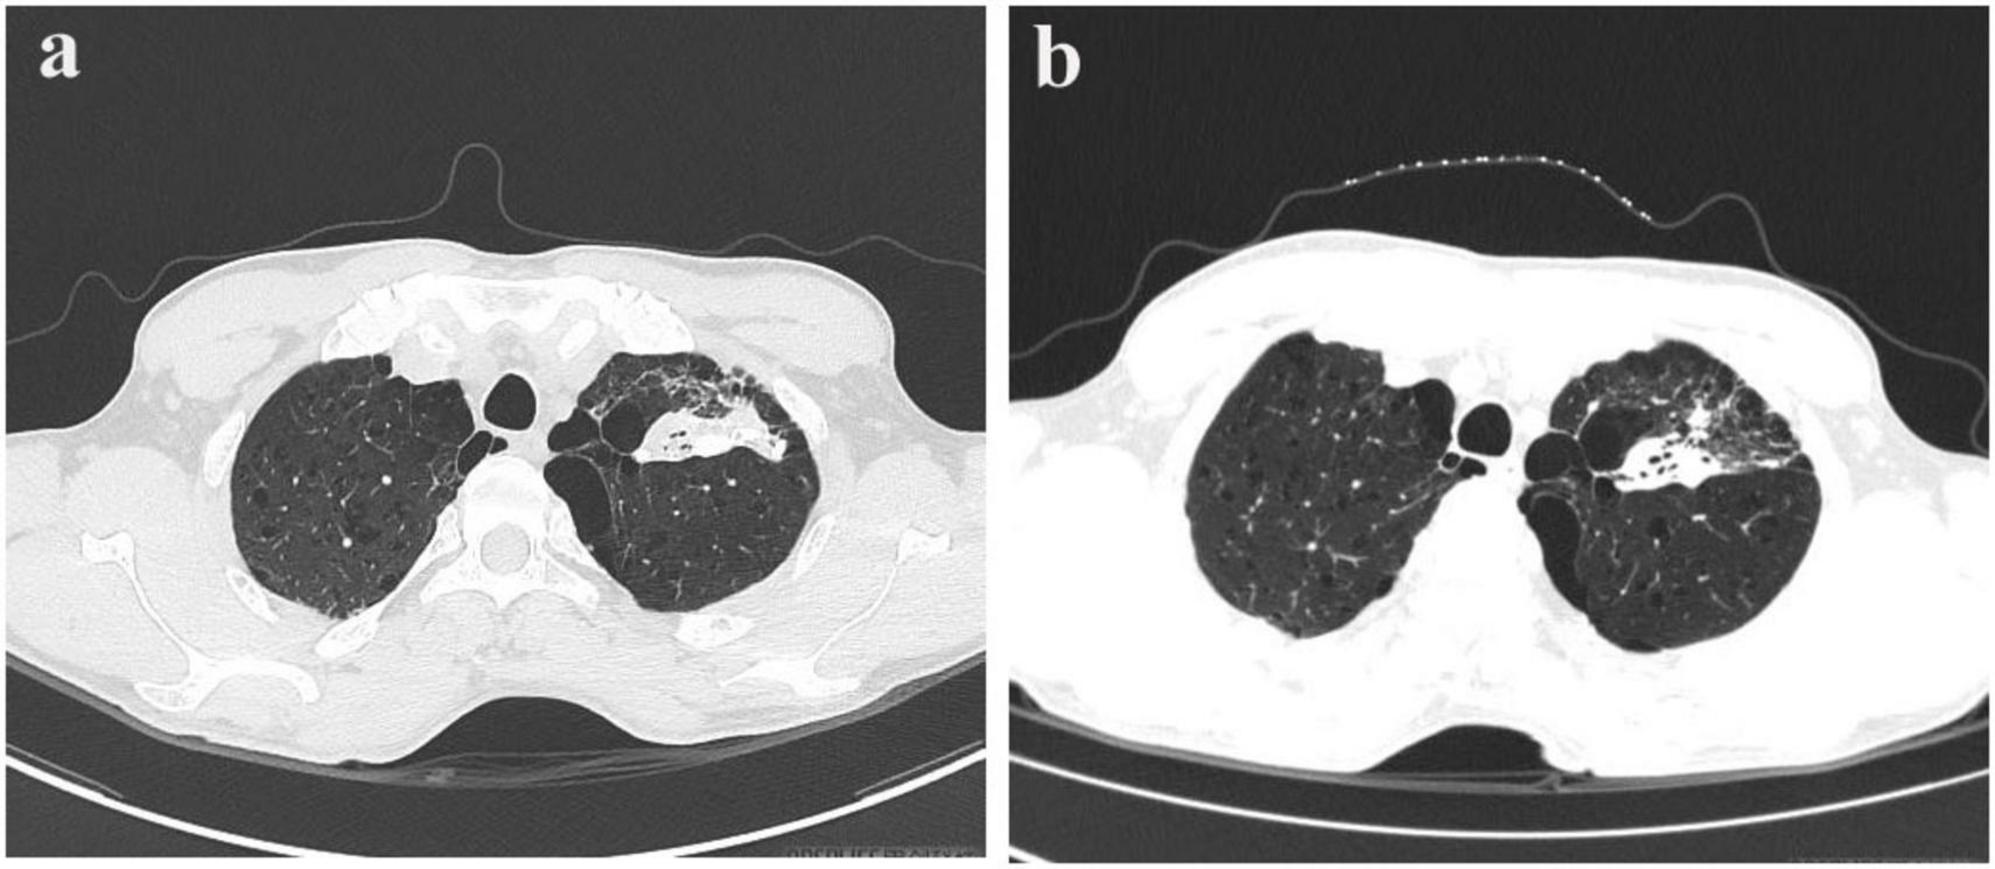

FIGURE 2

Pre- and post-treatment CT scans in pulmonary tuberculosis. (a) Chest CT scan on January 22, 2025. (b) Follow-up chest CT scan on March 26, 2025.

A bronchoscopy performed at our facility revealed no irregularities; however, the bronchoalveolar lavage fluid tested positive for TB-DNA, suggesting the presence of pulmonary tuberculosis. During a detailed history review, the patient disclosed having two cats for the past 2 years. Although there was no clear record of cat scratches, the possibility of CSD was considered due to negative results from PAS, silver methenamine, and acid-fast staining, along with the patient’s exposure to cats. Metagenomic pathogen detection workflow (MetaPath™)–a probe-enriched metagenomic next-generation sequencing (mNGS) method optimized for low-biomass specimens–successfully detected B. henselae sequences, rather than MTB, in formalin-fixed paraffin-embedded (FFPE) histopathological sections of a cervical lymph node specimen obtained externally. MetaPath™ technology of the cervical lymph node tissue detected sequences specific to B. henselae, identifying 82 sequences at a relative abundance of 7.19%, thereby confirming a diagnosis of CSD. The patient presented with lymphadenopathy, and pathological findings revealed granulomatous inflammation. The differential diagnoses include infectious etiologies such as tuberculosis, non-tuberculous mycobacterial infection, and fungal infections, as well as non-infectious conditions such as sarcoidosis and lymphoma. Based on comprehensive clinical, laboratory, radiological, pathological, etiological, and molecular evaluations, the patient final diagnoses included: (1) cervical lymphadenitis related to CSD; (2) pulmonary tuberculosis; and (3) emphysema with bullae. The patient commenced anti-tuberculosis therapy on January 18, 2025, following a regimen consisting of Isoniazid, Rifampicin, Pyrazinamide, and Ethambutol for 2 months, followed by a 4-month continuation of Isoniazid and Rifampicin. Subsequently, upon the detection of Bartonella species via MetaPath™ testing on January 23, 2025, ciprofloxacin was added for a duration of 4 weeks to address cat-scratch disease, targeting anti-Bartonella therapy. A follow-up CT scan of the chest and neck conducted on March 26 indicated partial resolution of the lesion in the left upper lung (Figure 1b) and nearly complete reduction of the enlarged lymph nodes in the right posterior cervical area (Figure 2b).